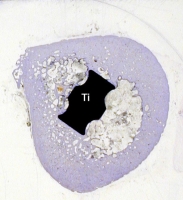

Querschnitt durch einen Titanschaft (Ti) und den umgebenden Oberschenkelknochen. Dieser umwächst das Implantat in direktem Kontakt: das Titan wird vom Knochen osseointegriert (mehrere Jahre postoperativ)

Abb. 14

Biologische Verankerung einer Pfanne: links die rauhe Titanoberfläche (Ti), rechts der aufgewachsene Knochen (B)

Auch bei der Titanpfanne kann eine ähnliche Einbautendenz durch körpereigenes Knochengewebe wie beim Schaft gesehen werden

(Abb. 14).

Bleibt diese Osseointegration über Jahre bestehen? Die folgenden Bilder illustrieren dies. Abb. 15a und b zeigen das Präparatröntgen einer 83-jährigen Patientin, welche 20,7 Jahre nach Implantation des Titaniumschaftes verstorben ist. Es finden sich stabile Verhältnisse. Die Abbildungen c und d zeigen, dass das Implantat (Ti) stabil im umgebenden Knochen verankert ist (Dünnschliffpräparate Prof. Dr. F. Lintner, Pathologie, Otto-Wagner-Spital). Dies bedeutet, dass die Osseointegration auch beim alten und sehr alten Menschen funktioniert.

Abb. 15d